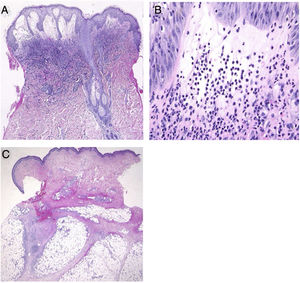

(A), Histological features showing dense neutrophilic infiltration throughout the edematous dermis (Hematoxylin & eosin, original magnification ×40). (B), Higher magnification showing the large number of infiltrating neutrophils (Hematoxylin & eosin, ×400). (C), Histological examination showing a septal panniculitis in the subcutaneous nodule in the lower extremity (Hematoxylin & eosin, ×20).

A 54-year-old female was admitted to our department, complaining of a 4-day history of up to 40.3 °C fever and cutaneous eruptions on the neck. The patient had been suffering from myelodysplastic syndrome (MDS), for which no drugs, including granulocyte-colony stimulating factor (G-CSF), were administered. Physical examination showed numerous concrescences of blisters clearly localized in the V-neck area (Fig. 1a, b). Painful erythematous nodules were scattered on the cheeks, but the tip of the nose was spared. Furthermore, there was one blister on the right forearm as well as painful erythematous nodules on the upper and lower extremities. She did not have any mucosal lesions or a prior history of recurrent oral aphthae. Laboratory examination showed a white blood cell count of 8,100/μL with 3% Band, 21% Seg, 9% Lym, 7% Mono, and 57% Blast, decreased levels of hemoglobin (8.6 g/dL) and platelets (108,000/μL), and increased levels of C-reactive protein (26.02 mg/dL). Blood culture was sterile. A biopsy specimen from the peripheral edge of the bulla on the neck showed a subepidermal bulla and dense neutrophilic infiltration in the upper to mid-dermis (Fig. 2a, b). Immature myeloid cell infiltration was not detected. Infiltration of histiocytes/histiocytoid cells was not observed, and immunohistological examination showed scattered CD68- and MPO-positive cells which were not prominent. Additionally, another biopsy taken from the lower leg showed infiltration of inflammatory cells, mainly lymphocytes, around the vessels in the septa of the subcutaneous fat tissue (Fig. 2c). Hematological examination and bone marrow biopsy revealed transformation from MDS into acute myelocytic leukemia, and chemotherapy including prednisolone was immediately started in the hematology department. After about one week, all of the bullous lesions were re-epithelialized.

The present case developed a sudden onset of skin lesions, which histopathologically showed a predominant neutrophilic infiltration without leukocytoclastic vasculitis. In addition, fever, elevated C-reactive protein, and rapid response to systemic steroids were observed. White blood cell count was within the upper limit of the normal range but two times higher than the usual value. Thus, the patient fulfilled the criteria for Sweet syndrome (SS). Cutaneous lesions of SS associated with myelodysplasia tend to be vesicular, bullous, or erosive. The present case developed bullous SS, simultaneously with the blastic crisis of MDS. Of interest, the lesions showed a peculiar distribution of well-circumscribed erythema in the V-neck area not protected by clothes during the season when the dose of ultraviolet radiation is increased in Japan, which was considered to be a photo-Koebner phenomenon. Only several cases of photo-induced or photo-distributed SS have been reported, in which both ultraviolet A and ultraviolet B were candidates for induction of skin lesions.1–3 Although phototesting was not performed in the present case, the patient had no previous history of photosensitive dermatitis or of taking drugs that can induce photosensitive eruptions. To our knowledge, the current report is the first case of photolocalized bullous SS. The direct action of ultraviolet is speculated to activate and recruit neutrophils via interleukin-8, tumor necrosis factor-α, E-selectin, interleukin-1α, and G-CSF4,5 as well as ultraviolet-induced local immunosuppression. Finally, the patient concurrently developed infiltrative erythematous nodules on the face and extremities. Biopsy showed septal panniculitis with lymphocytic infiltration without neutrophil infiltration in either dermis or subcutis; however, all of the concurrent lesions were considered to be part of the same spectrum.